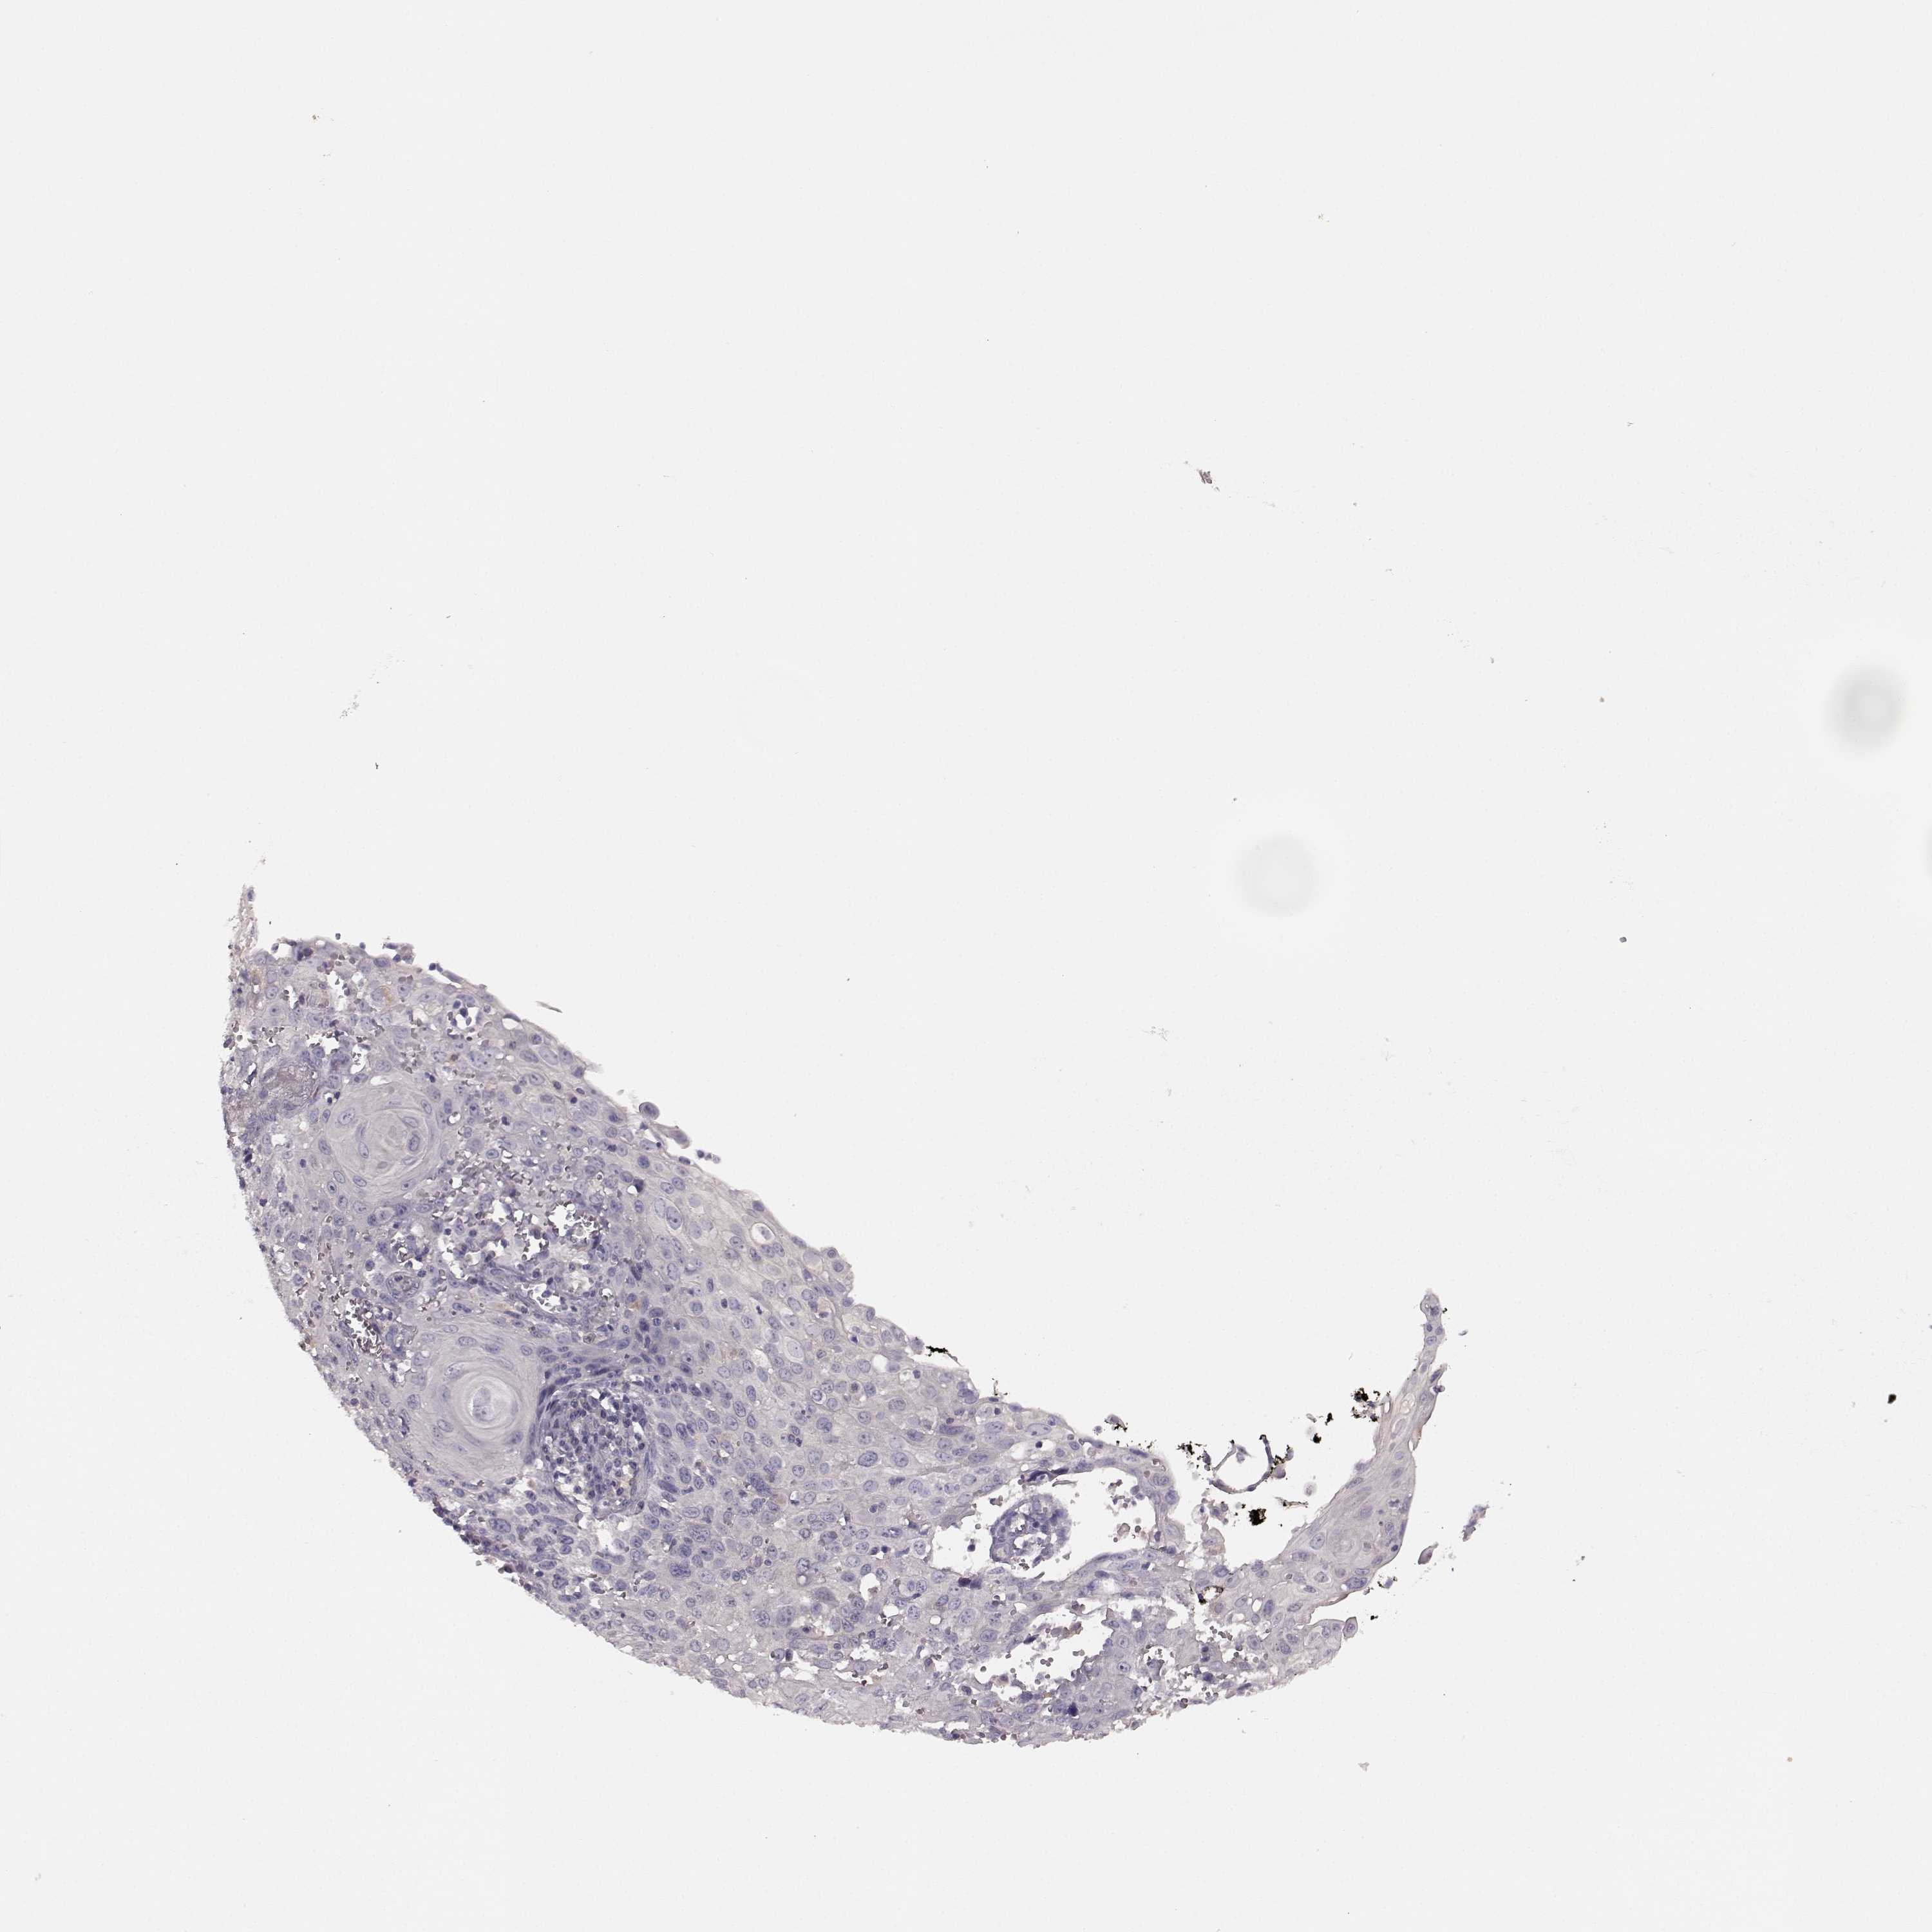

CERVICAL CANCER - Protein expressioni

A mouse-over function shows sample information and annotation data. Click on an image to view it in a full screen mode. Samples can be filtered based on level of antibody staining by selecting one or several of the following categories: high, medium, low and not detected. The assay and annotation is described here.

Note that samples used for immunohistochemistry by the Human Protein Atlas do not correspond to samples in the TCGA dataset.

Antibody stainingi

Antibody staining in the annotated cell types in the current human tissue is reported as not detected, low, medium, or high, based on conventional immunohistochemistry profiling in selected tissues. This score is based on the combination of the staining intensity and fraction of stained cells.

Each image is clickable and will lead to virtual microscopy that enables deeper exploration of all samples and also displays staining intensity scores, fraction scores and subcellular localization as well as patient and tissue information for each sample.

Antibody HPA045339

Staining

High

Medium

Low

Not detected

Intensity

Strong

Moderate

Weak

Negative

Quantity

>75%

75%-25%

<25%

None

Location

Nuclear

Cytoplasmic/membranous

Cytoplasmic/membranous,nuclear

Squamous cell carcinoma, NOS

Adenocarcinoma, NOS